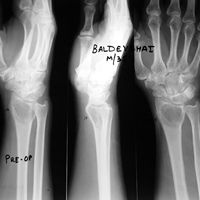

Case:1 GCT L/E Radius

Pre-Op

One and Half month follow up

One and Half year foll

2 years Follow-Up